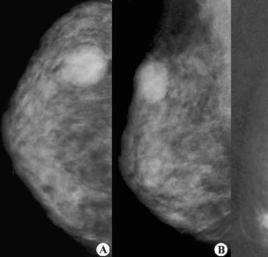

(3)鉬靶X線攝片及其他影像檢查,可幫助診斷。必要時可作腫塊針吸細胞學檢查或活組織病理檢查,以最終明確診斷。

乳腺纖維囊腫的乳房腫塊發病時間短,腫塊增大迅速,診斷要與乳癌作鑑別,需要臨床醫師有足夠的乳腺纖維囊腫經驗,鉬靶X線攝片對診斷有幫助,可見不規則增強陰影中有圓形透亮環,但有時不易與乳癌透亮環鑑別,X線也不易將乳腺周圍纖維增生明顯的孤立性囊腫與纖維腺瘤相鑑別,彩超高頻聲像圖對診斷纖維囊腫的正確率較高,顯示無回聲腫塊,周圍無高速低阻的血流圖像。無損傷且隨訪方便。